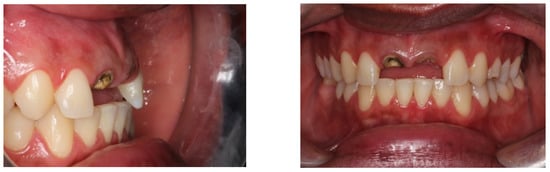

3. Results

Result and Follow-Up